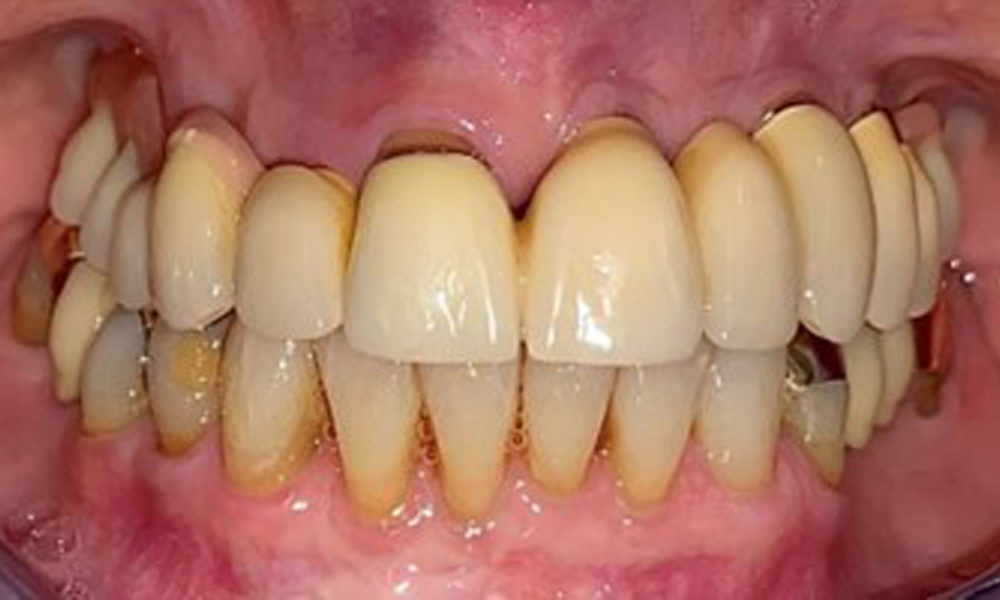

Die Patientin wurde vor über 25 Jahren mit einer kombinierten herausnehmbare Implantat-Teleskopprothese im Oberkiefer versorgt (Abb. 1, Abb. 2, Abb. 3) und ist sehr glücklich über ihren Zahnersatz. Im Unterkiefer hat die Patientin einen suffizienten festsitzenden Zahnersatz. (Abb. 4)

Der dentale Befund stellt sich wie folgt dar: Kombinierte herausnehmbare Implantat- und zahngetragene Teleskoparbeit auf Implantaten 15, 13, 21, 23, 24, 25 und Zahn 11 (Abb. 1, Abb. 2, Abb. 3). Im Unterkiefer ist die Patientin mit einem festsitzenden Zahnersatz versorgt. 37–34 sowie 45–47 haben suffiziente Brücken (Abb. 4). Kronenränder sind intakt, aktive kariöse Läsionen sind nicht vorhanden. An Zahn 43 zeigt sich eine Compositefüllung mit Randspalt. Im Unterkiefer liegen Rezessionen mit freiliegender Wurzeloberfläche zwischen 1 – 3 mm vor. Dies trifft auch für 11 zu.